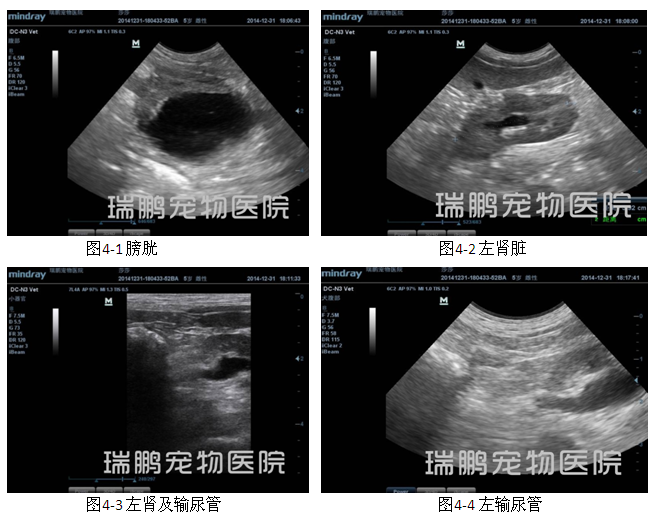

腹部超声波检查结果显示,膀胱壁回声正常、膀胱内可见一个直径约1.28 cm的高回声团块后带声影;左肾肾盂轻度扩张、肾脏结构完整、被膜完整平滑,左侧输尿管出肾门约0.5 cm处可见一个高回声团、直径约0.17 cm;右肾结构不清晰、整体回声增强 、被膜完整平滑;肝脏被膜完整平滑、肝实质回声均质、胆囊壁回声正常、胆囊内为均质无回声;脾脏回声均质、被膜完整平滑。